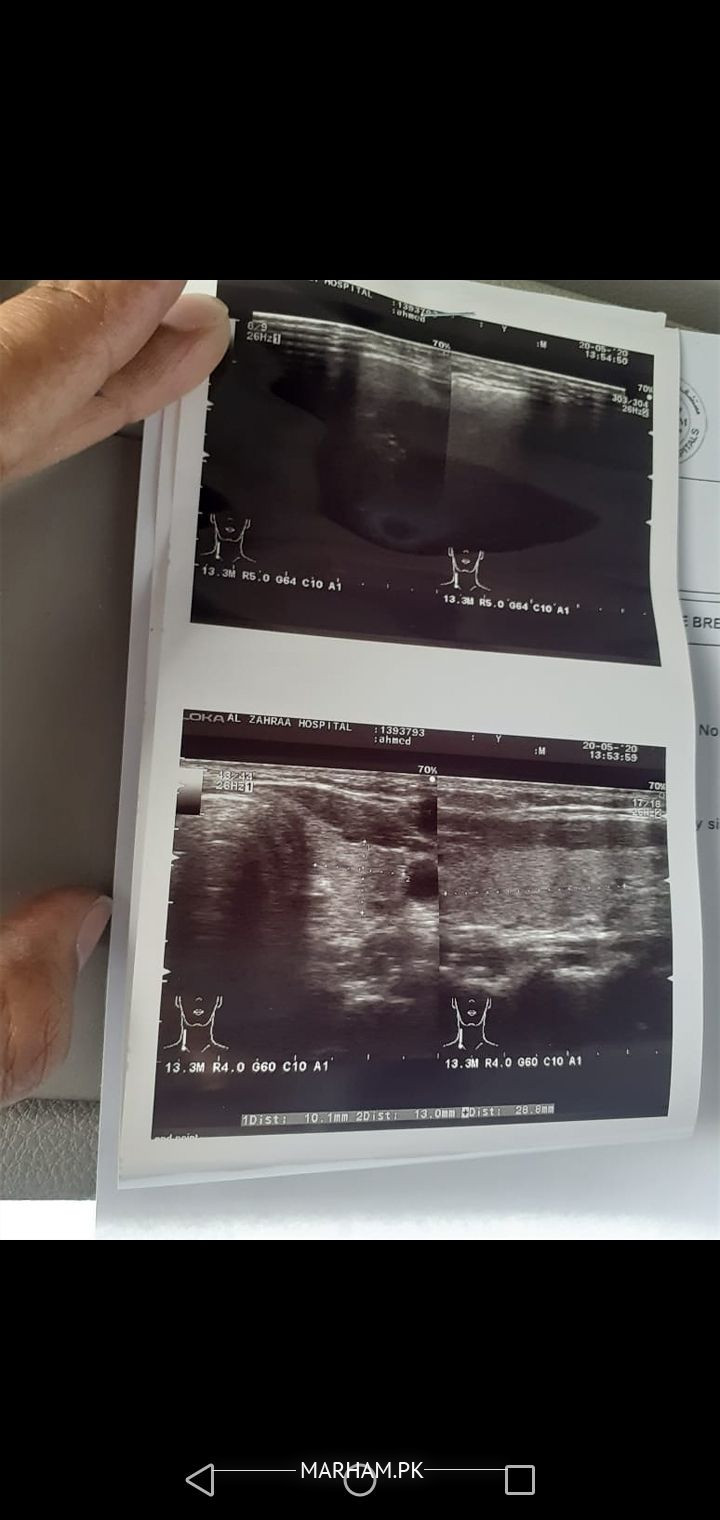

Salam alikum. Mere husband ko 6 months se gally m left side pr jallan or dard hai, 4 months se antibiotics madicine bhi kha rahe hein but abhi tak dard or jallan m koi frk nahi aya infect or ziada bhrti ja rahi hai or left bazu or chest m bhi drd wgra feel horaha hai. Ultrasound m 18 mm ka lymph node show huwa neck m... Ab aagy hme kiya krma chahiye plz koi bataye. Please help

Yeh test likh diya hai doctor n kiya yeh theek hai?